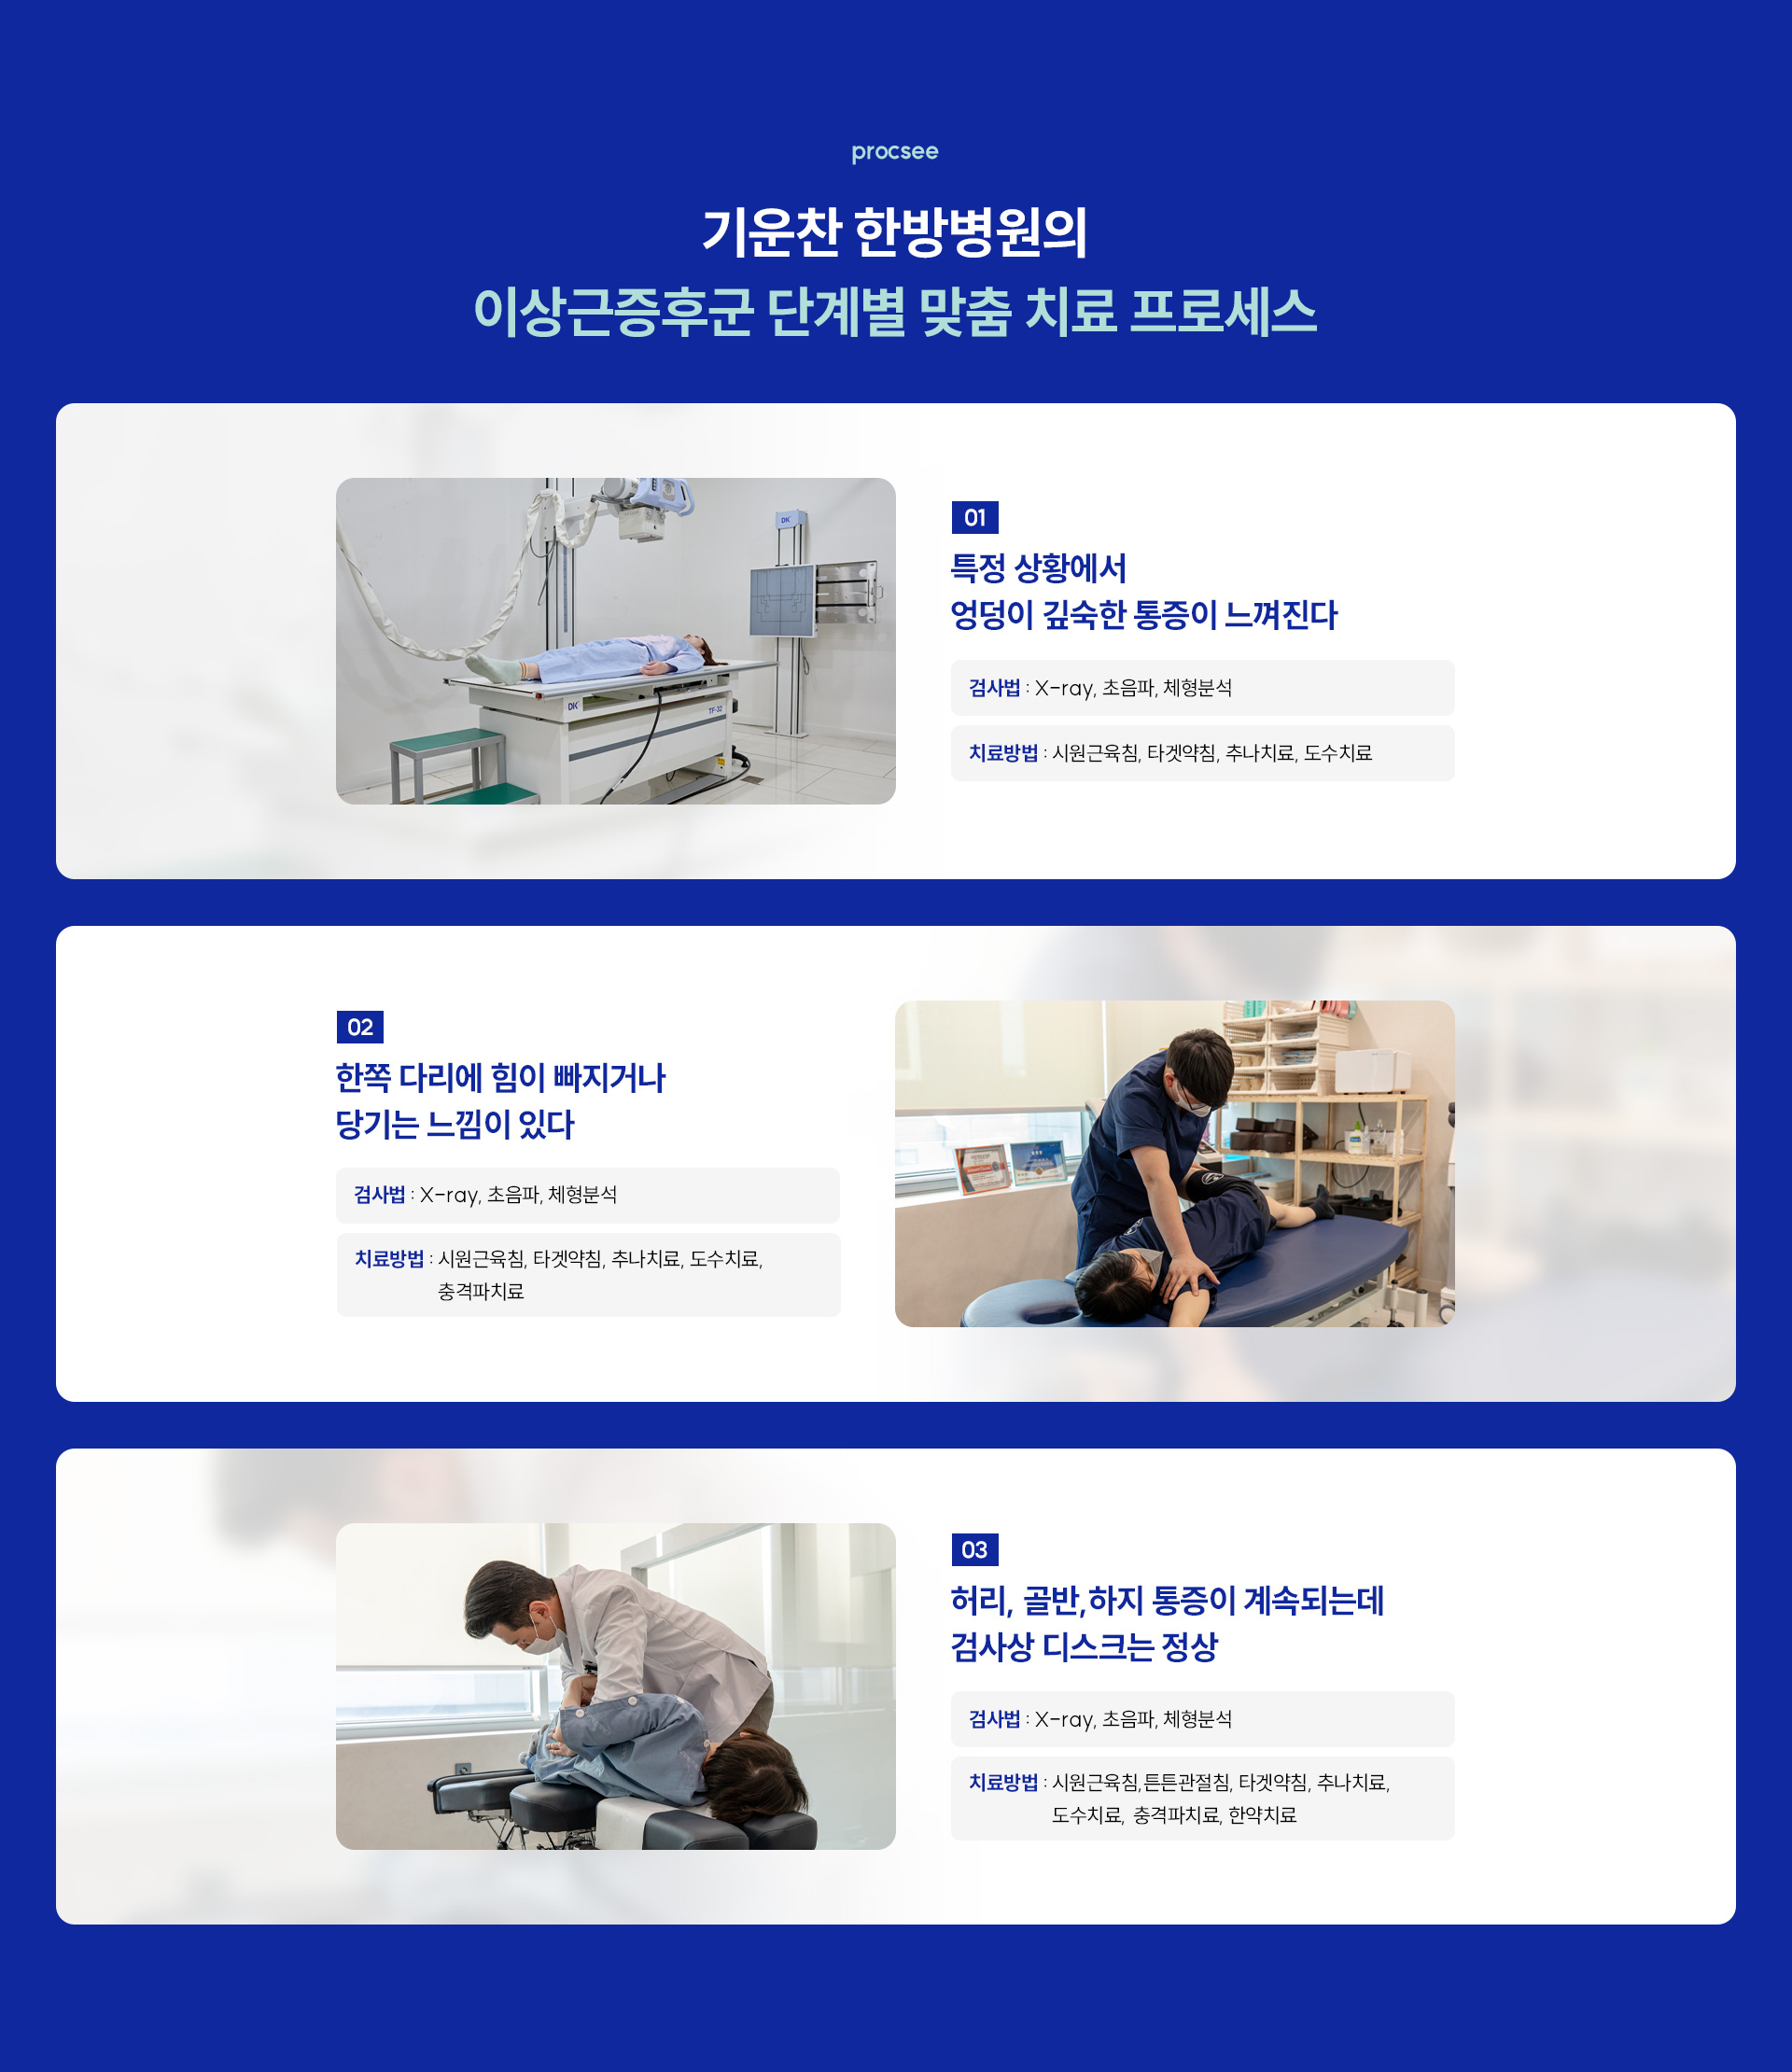

고관절주위염은 추나치료, 침치료, 약침치료를 통해 염증을 효과적으로 완화할 수 있습니다.

기운찬한방병원에서는 신체의 회복력을 기반으로 한 비수술적 치료를 시행하며,

스테로이드 약물을 사용하지 않고도 증상을 개선할 수 있는 것이 큰 장점입니다.

엉덩이 깊숙한 통증, 한쪽 다리 힘 빠짐, 사타구니 뻐근, 고관절 뻣뻣, 디스크 정상인데 통증, 골반 하지 통증, 이상근증후군 한방, Piriformis Syndrome, 고관절주위염, 시원근육침, 튼튼관절침, 타겟약침, 체형분석, 한방재활 외과 협진, 365일 진료, 구월동 고관절 한방